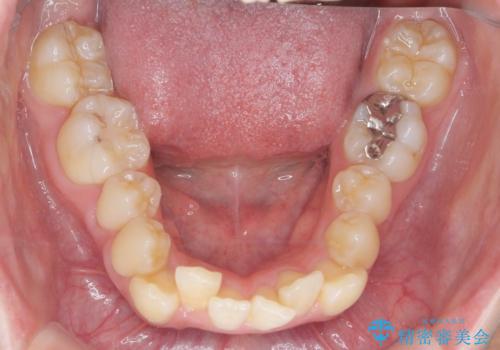

前歯のがたつきをマウスピース矯正できれいに!

- 目立つ前歯のがたつきを改善したい、と矯正治療を希望され来院されました。

今回の治療ではシミュレーションでしっかりと検討した結果、下顎は前歯を1本抜去し仕上げる治療計画としました。